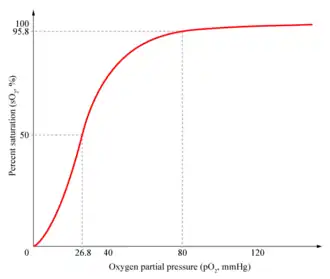

| Relação entre a pressão parcial de oxigênio em sangue (pO2) e a saturação das hemoglobinas com oxigênio (sO2%). O valor normal de sO2 é maior que 95% em sangue arterial e valores menores a 90% indicam insuficiência respiratória. | |

- Tipo I (hipoxêmica): pressão parcial de oxigênio (PaO2) é menor a 60 mmHg;

É também conhecida como insuficiência alveolocapilar é caracterizada por hipoxemia, quando o a Pa02 é menor que 60 mmHg, no entanto a ventilação está normal, ou seja, o nível de PaCo2 está normal ou baixo. É a forma mais comum de IRP e podem estar associadas a todas as doenças que colapsem as unidades alveolares.